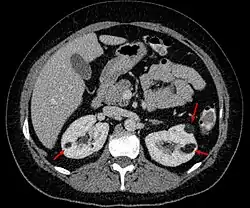

Angiomyolipoma in both kidneys (arrows) in computer tomography. The tumours are hypodense (dark) due to fat content.